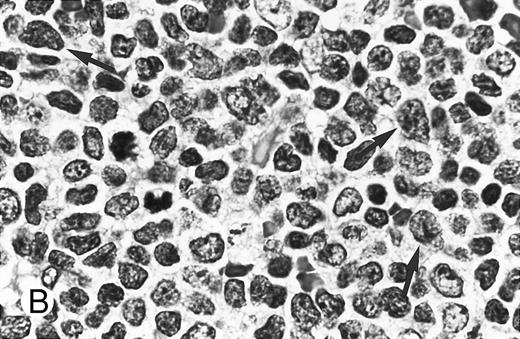

Cytologically, MCL nuclei were round to ovoid, slightly irregular with inconspicuous nucleoli and slightly clumped chromatin (Fig 3A). Cytoplasm was scant. Larger cells with medium-sized nuclei, fine chromatin, inconspicuous nucleoli, and scant cytoplasm were present in most cases to varying degrees. These cells resembled lymphoblasts rather than large noncleaved cells, prolymphocytes, or paraimmunoblasts. In some cases, lymphoblast-like cells were present in significantly increased numbers (Figs 3B and C), implying cytologic transformation (discussed below). Mitoses were easily found in the majority of cases, the prognostic significance of which is discussed below.

Composite photograph showing the cytologic features of MCL. (A) Typical cytology of MCL characterized by cells with small, slightly irregular nuclei, inconspicuous nucleoli, and minimal cytoplasm. Note the frequent epithelioid histiocytes (arrows). (B) MCL with prominent features of transformation, but not clearly blastic. Increased numbers of larger cells with fine chromatin and inconspicuous nucleoli are shown (arrows). (C) Blastic MCL. Note the cytologic resemblance to lymphoblastic lymphoma. (D) OS of 80 patients with MCL based on the presence of blastic features. The 5 cases designated as blastic MCL were associated with a significantly shorter survival when compared with that of all others (n = 75) including those with features of transformation as shown in (B).

Blastic features.Virtually all 80 cases had at least a few cells with larger nuclei, finer chromatin, and inconspicuous nucleoli; however, in the majority of cases, these cells were present in small numbers. When present in increased numbers, these lymphoblast-like cells were almost always accompanied by an increase in mitotic activity and, occasionally, the presence of tingible body macrophages (Fig 3B). These cases were designated as having prominent features of cytologic transformation. In a minority (n = 5), the blastic cells were so numerous that the histology was nearly indistinguishable from that of lymphoblastic lymphoma; these cases were designated blastic MCL (Fig 3C). The mean MS in the blastic MCL cases was 57.

The OS was significantly shorter for those cases with blastic morphology (Fig 3D). No statistically significant differences in survival were observed between the 16 cases that were transformed to some degree but not truly blastic and the remaining 59 cases that showed no evidence of transformation.